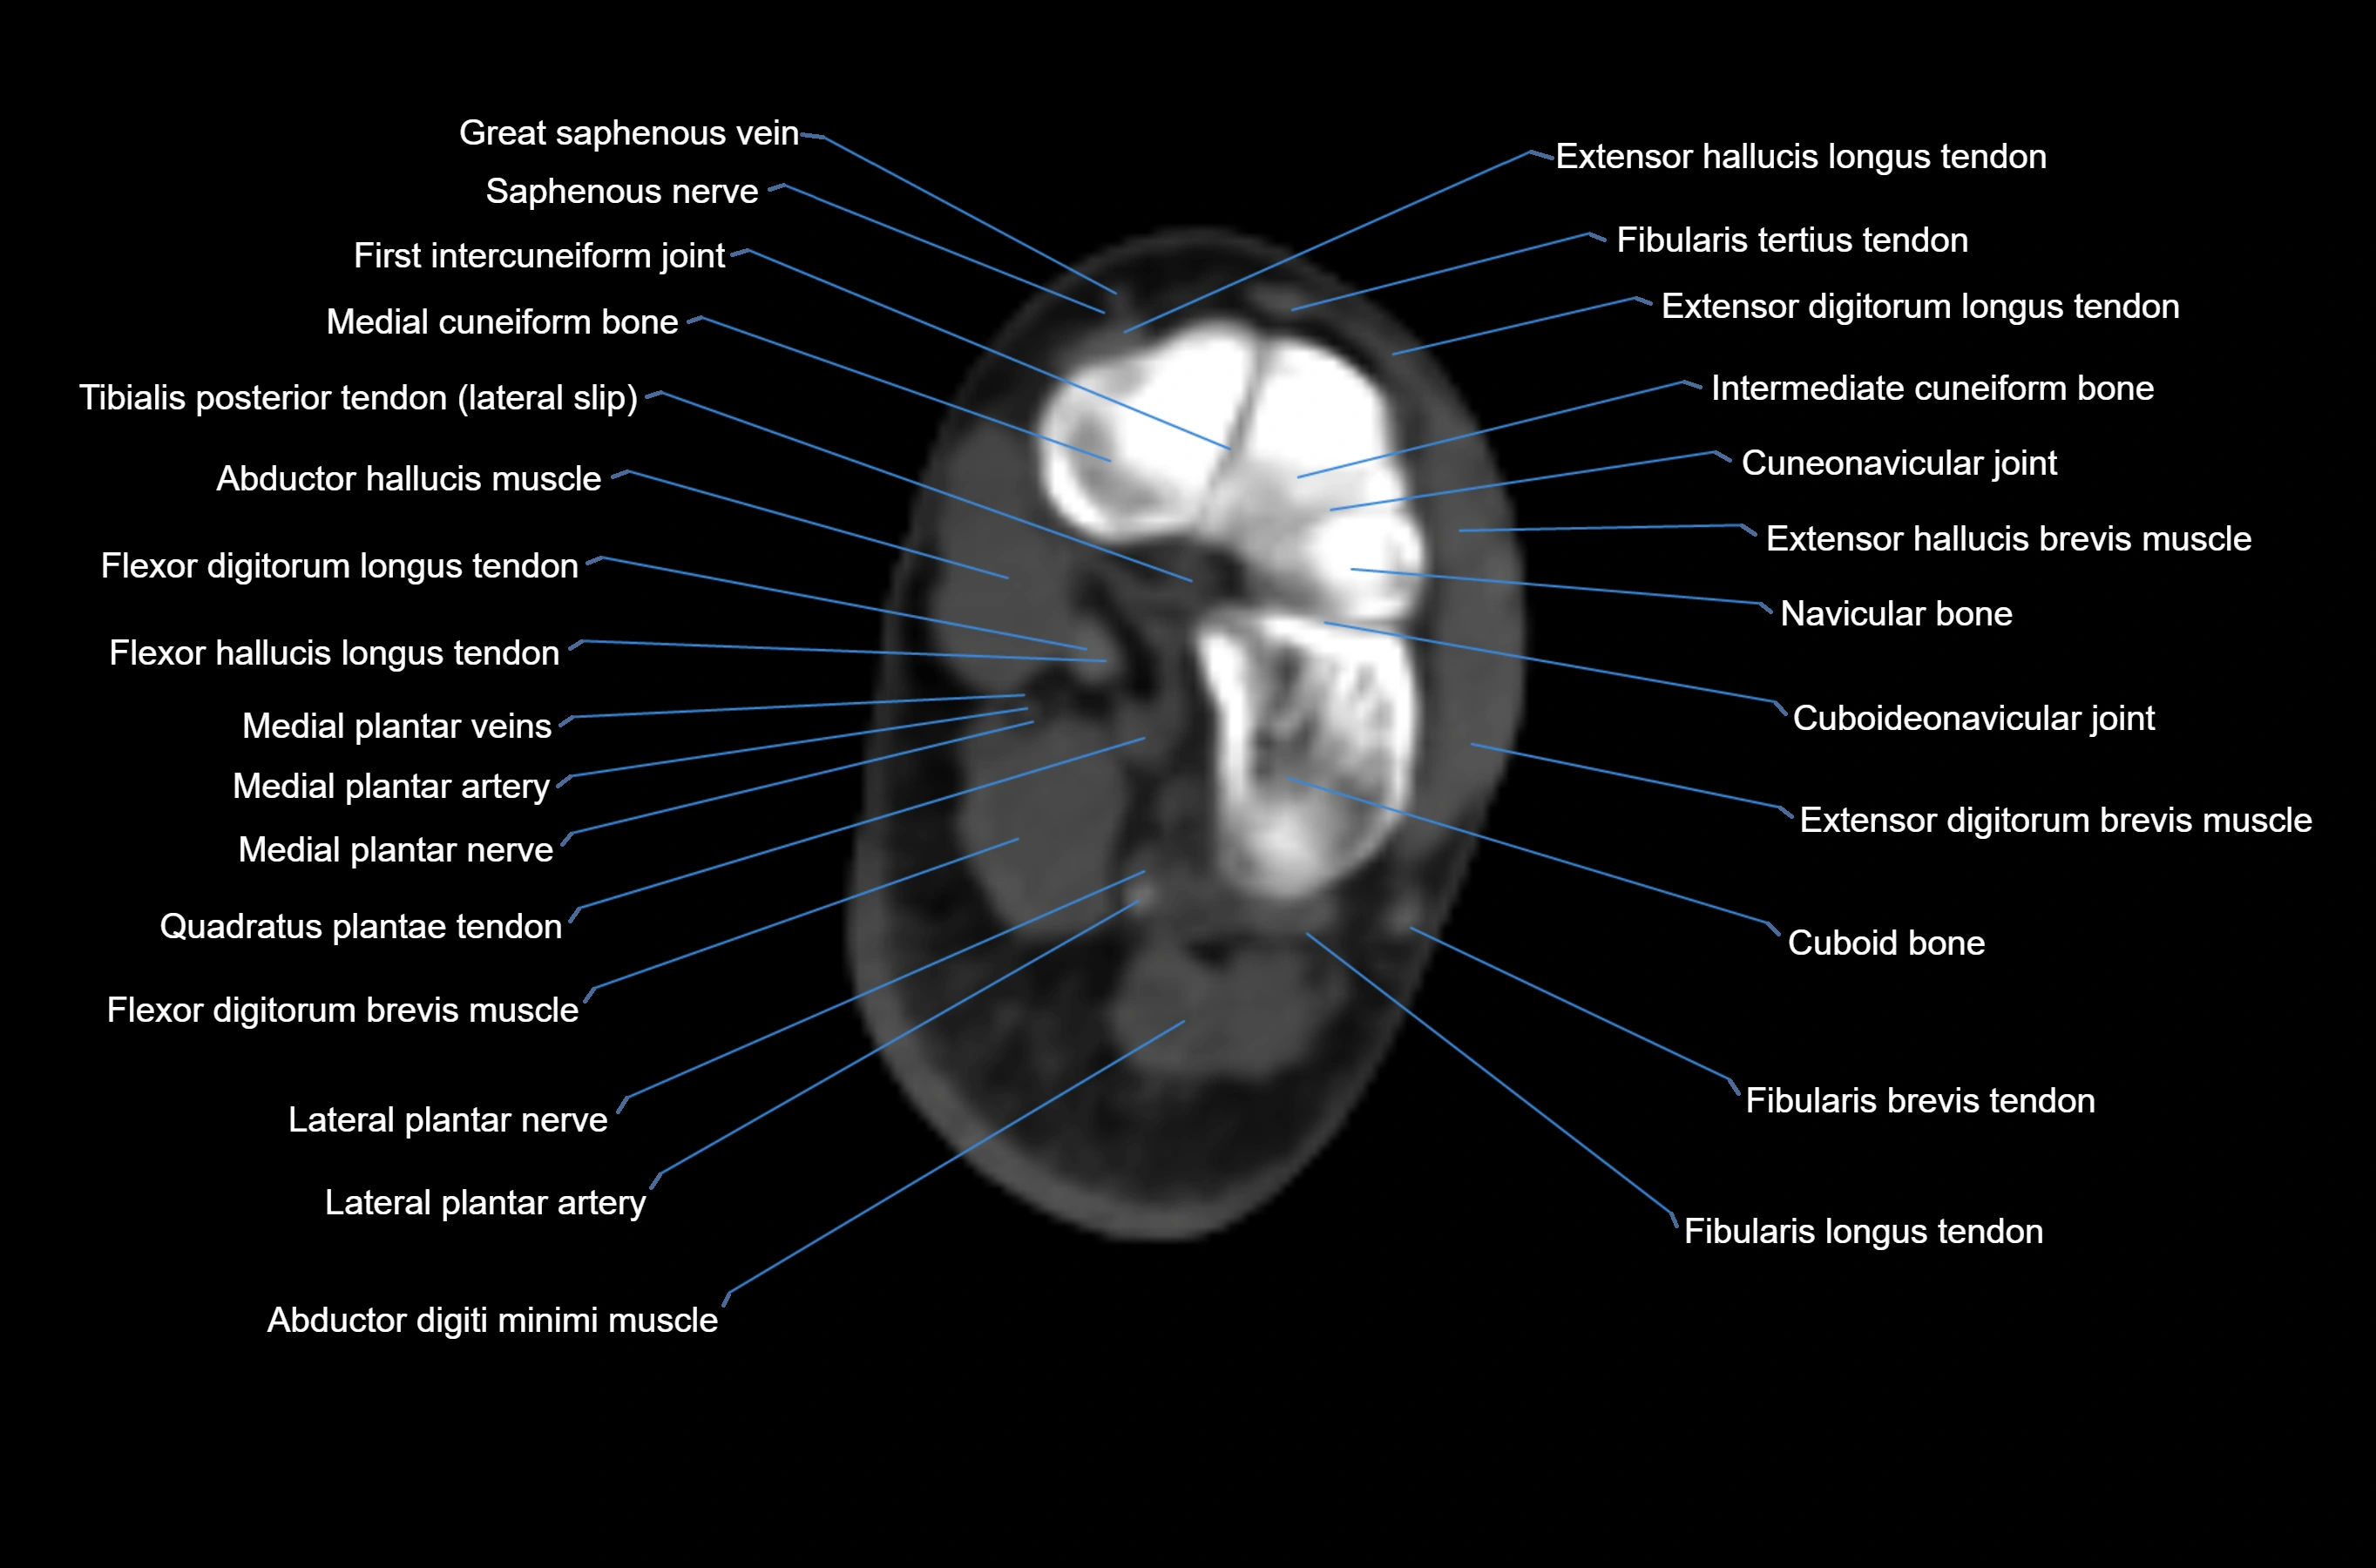

MRI image

CT image